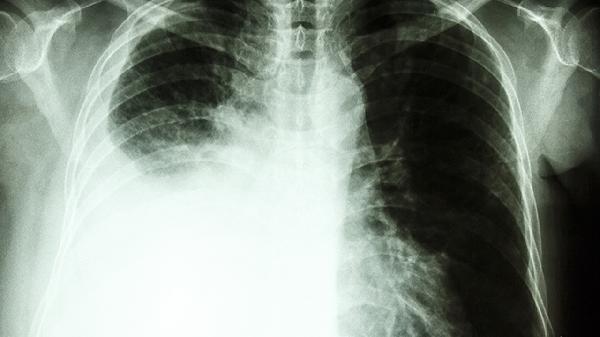

对于阴虚型肺结核患者的低热、咯血症状,该药可辅助西药治疗缓解不适。需注意结核病必须规范使用抗结核药物,养阴清肺丸仅作为对症支持治疗。